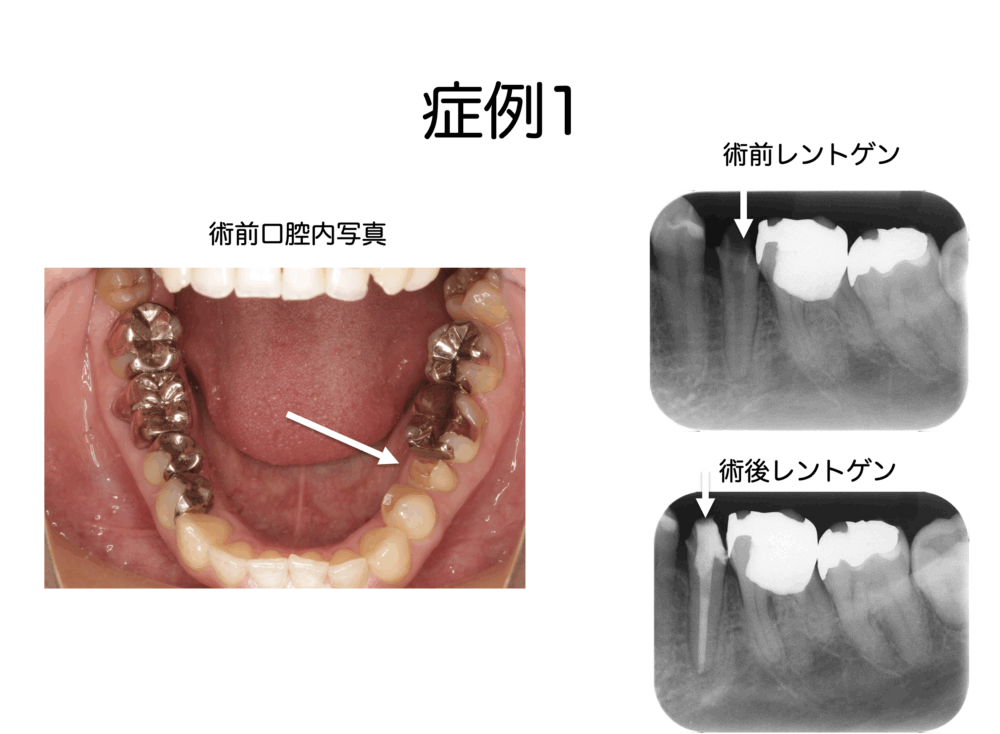

歯髄(歯の神経)は残せるか?残せないか?〜診査診断の大切さ 歯髄壊死編②〜 2020.02.27 かむと痛い / 根管治療 / 歯髄壊死 / 虫歯 / 院長ブログ ももこ歯科のブログを読んでくださる皆様、いつもありがとうございます。 前回、歯髄壊死の診査や症状についてお話ししました。 今回は、実際にあった歯髄壊死の症例を挙げて、いつもどうやって診断をしていくか、順番にお話しします。...続きを読む